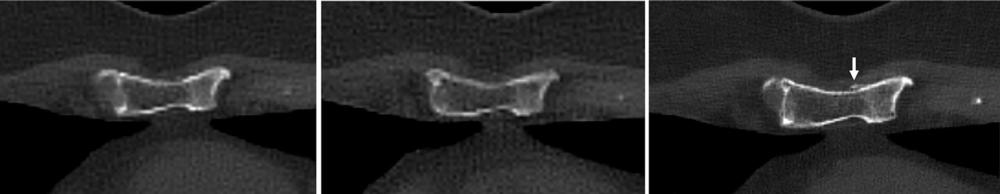

Figure 6. Images in a 60-year-old woman with multiple myeloma. Two-millimeter noncontrast-enhanced axial energy-integrating detector CT image (left), 2-mm noncontrast-enhanced axial photon-counting detector (PCD) CT image (center), and noncontrast-enhanced axial 0.6-mm PCD CT image (right) show representative pathologic myeloma-induced healing pathologic fracture through the lower sternum. Cortical irregularity is evident on all three reconstruction images; however, the associated callus is only visible on the 0.6-mm PCD CT reconstruction image (right; arrow).